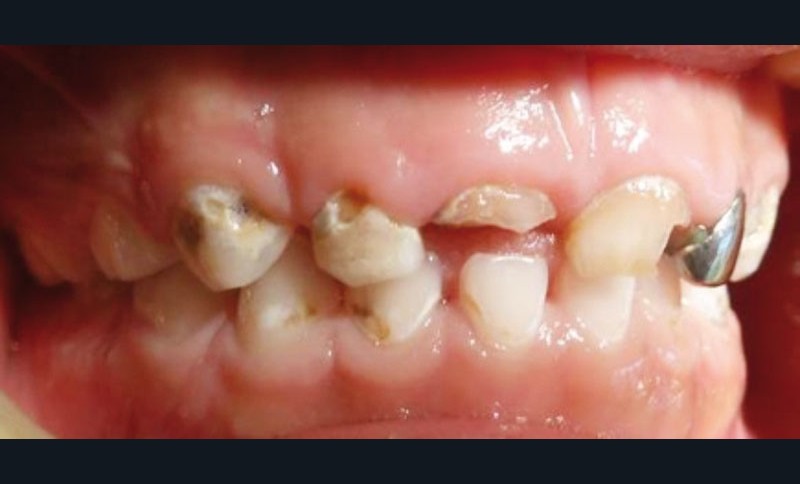

La perte d’une ou plusieurs dents temporaires avant leur date d’exfoliation physiologique est fréquemment observée chez l’enfant. Ces situations cliniques sont principalement associées à la maladie carieuse et aux traumatismes alvéolo-dentaires, voire aux deux simultanément [1, 2] (fig. 1). Dès le plus jeune âge dans le cas de la carie de la petite enfance, des lésions carieuses sévères et multiples peuvent nécessiter l’avulsion d’une ou plusieurs dents temporaires antérieures et/ou postérieures affectées par des complications pulpo-parodontales ou qui ne peuvent être restaurées [3]. Suite à un traumatisme en denture temporaire, le remplacement de la ou des dents antérieures est fréquent. En complément, les agénésies dentaires et certaines anomalies dentaires héréditaires peuvent nécessiter une réhabilitation prothétique transitoire [1, 4].